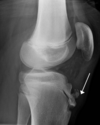

Grey Turner’s sign

Flank ecchymosis

Acute pancreatitis